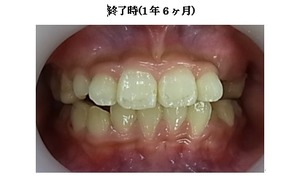

☆終了時(1年6ヶ月)